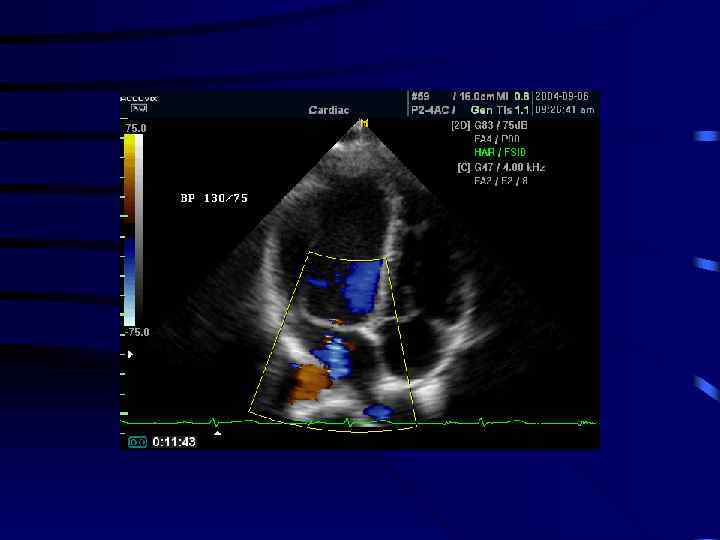

Допплерография

ВС: изменение потока крови при допплерографии (На примере митрального клапана) норма В обратном направлении определяется турбулентный Турбулентный поток за счет поток с широким основанием уменьшения площади отверстия МС: регургитация крови при

Цветное панорамное сканирование